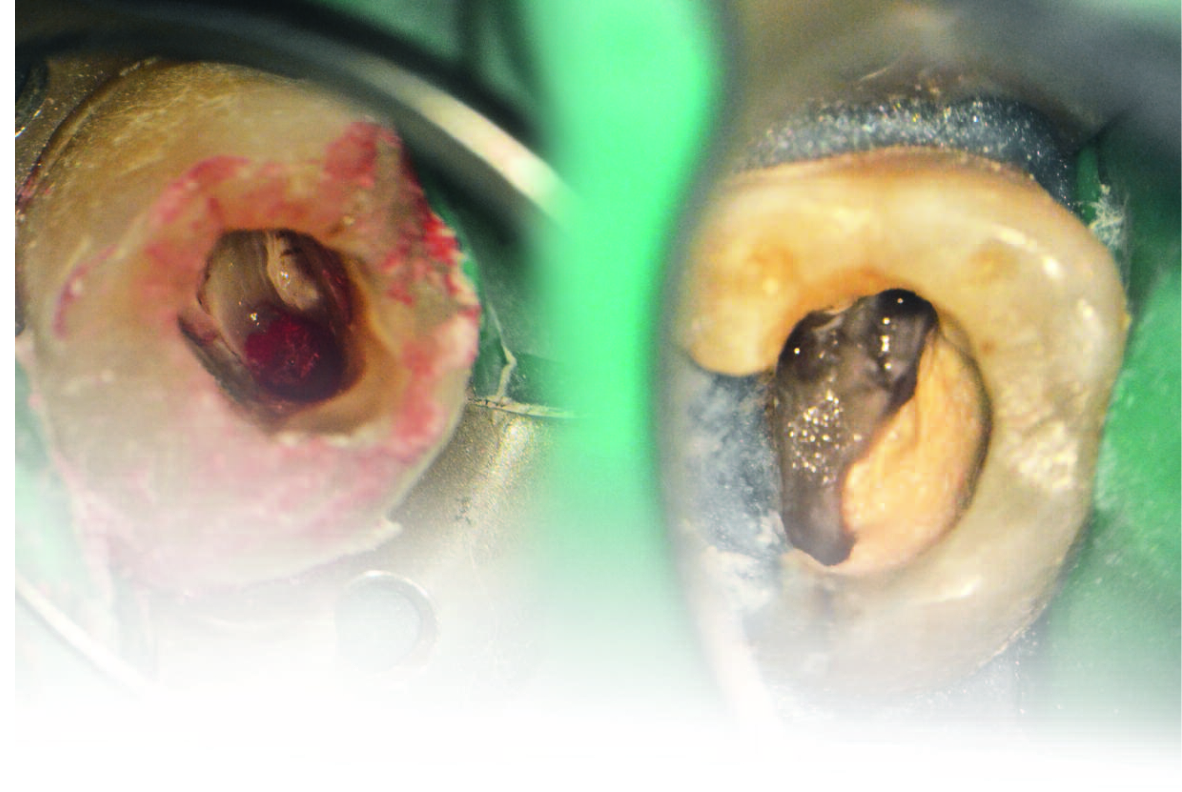

Фото 2 і 3. Перфорація у дистально-піднебінній ділянці.

Кровотеча пародонту була під перфорацією зупинена

гідроксидом кальцію, змішаним із пропіленгліколем. Одразу після цього знайшли

піднебінний канал (Фото 4), і перед тим, як знайти щічні канали, перфорацію

закрили ясенним бар'єром (Фото 5).

Фото 4. Тканину пародонту стабілізовано, піднебінний

канал виявлено.